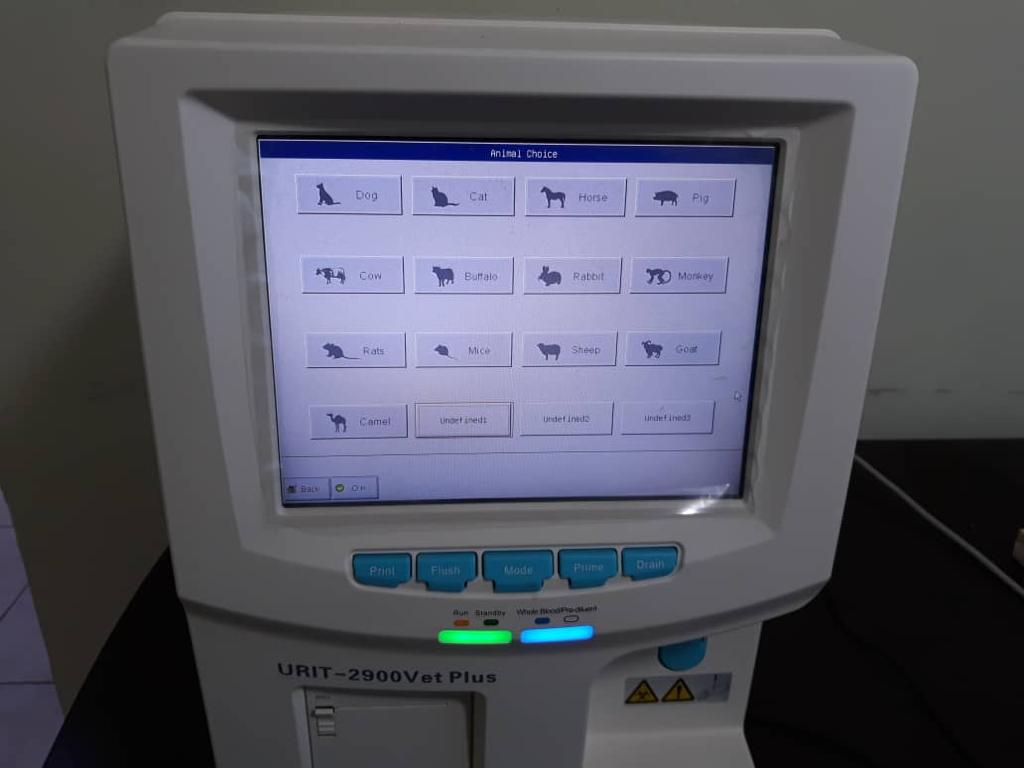

علاوه بر سگ و گربه، حیوانات خانگی خاص مانند خرگوش، همستر، پرندگان زینتی و خزندگان نیز توسط دامپزشکان متخصص ویزیت میشوند.